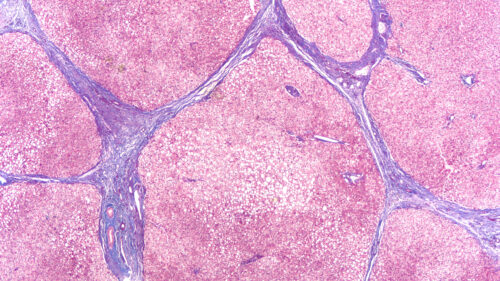

La fibrosis quística es una enfermedad multisistémica que afecta el epitelio del tracto respiratorio, el páncreas, el intestino, el sistema hepatobiliar y las glándulas sudoríparas exocrinas. Las morbilidades que surgen de la fibrosis quística incluyen enfermedad pulmonar obstructiva progresiva con bronquiectasia, hospitalizaciones frecuentes por enfermedad pulmonar, insuficiencia pancreática y desnutrición, sinusitis y bronquitis recurrentes, e infertilidad masculina. La enfermedad pulmonar es la principal causa de morbilidad y mortalidad en la fibrosis quística.